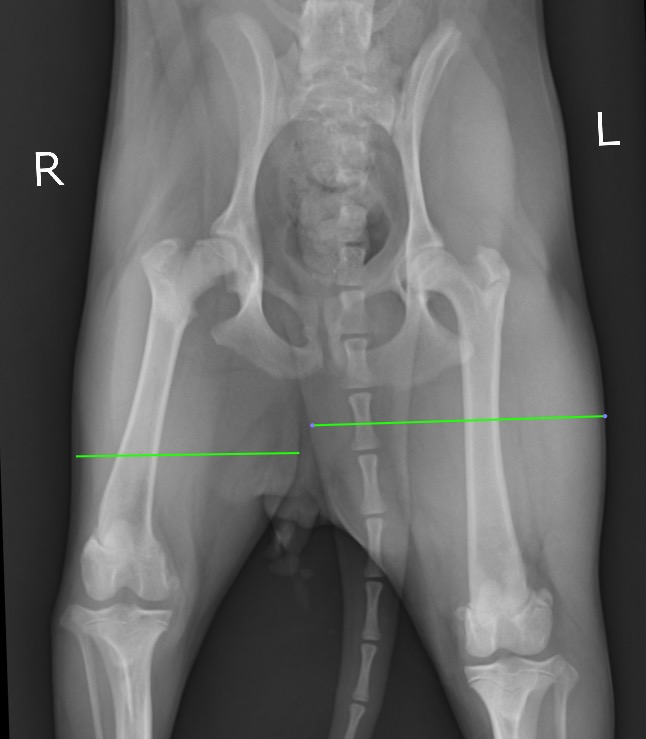

整形外科学的検査において、右後肢の負重性跛行、右殿筋~大腿にかけての筋萎縮、右股関節の伸展痛が認められたためX線検査を実施いたしました。

X線検査において右大腿骨頭の不整、骨萎縮、X線透過性の変化が認められ、(赤矢頭)

背景にレッグカルベペルテス病(LCPD、無菌性虚血性大腿骨頭壊死症)(以下LCPD)の存在が疑われました。

また右の大腿部の筋肉量が左に比べてだいぶ細いこともよく分かります。(緑線)

痛みのある右の後ろ足をかばいなるべく体重をかけず使わないように生活していた結果の筋萎縮だと考えられます。